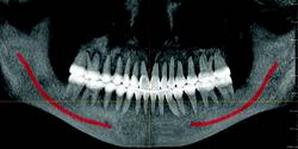

CBCT imaging provides comprehensive data and the ability to dynamically manipulate that data, viewing anatomy from multiple perspectives. Diagnosis of TMJ condition and disorder or jaw pathology along with the evaluation of orthodontic cases, airways, impacted teeth and periodontal defects are all facilitated through the use of CBCT imaging.

A larger field of view CBCT is usually most appropriate in the specialty practice, due to the fact that compared to smaller field-of- view units, more of the patient’s maxillofacial anatomy is captured in each scan.